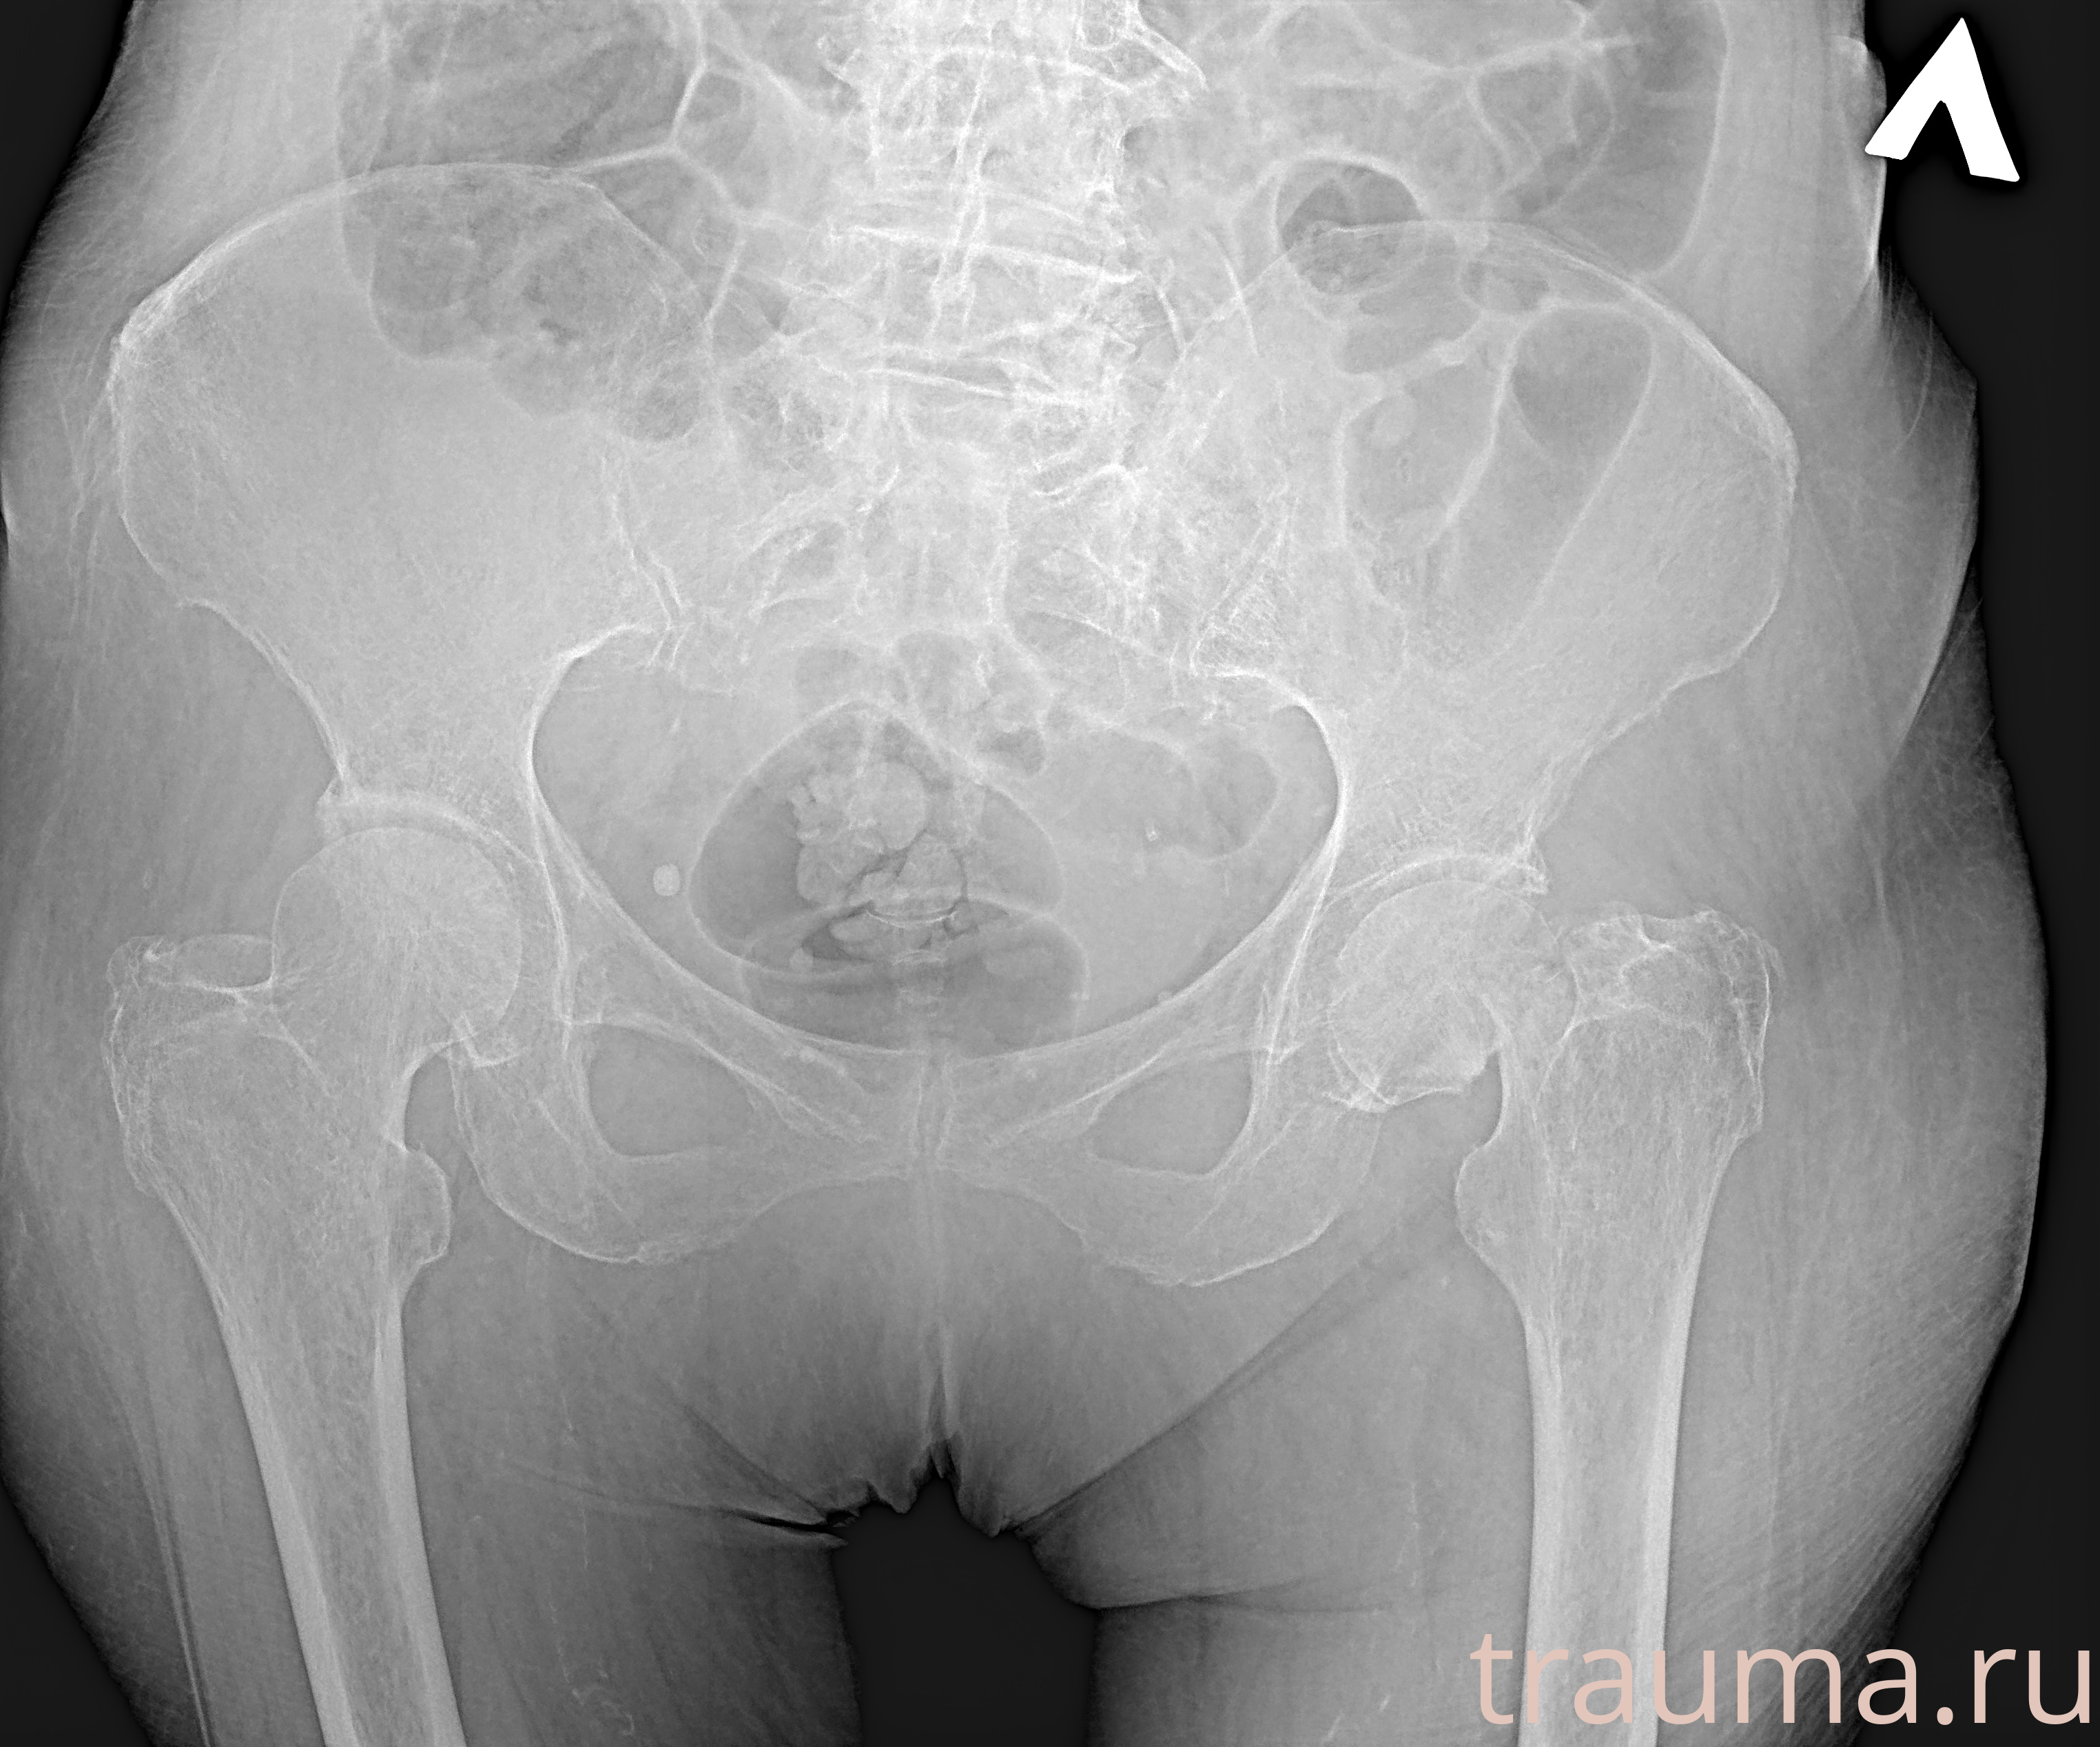

Рентгенограммы

Рентген на дому: по вашему адресу приезжает врач-рентгенолог, травматолог-ортопед с мобильным рентгеновским аппаратом, проводит диагностику травмы или заболевания, делает необходимые рентгенограммы, дает рекомендации по дальнейшему лечению. Получить качественные снимки в домашних условиях возможно благодаря уникальной методике, разработанной МосРентген Центром для института  Склифосовского